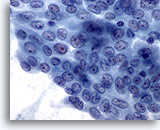

Verdenking van maligniteit

Als het monster niet hypercellulair is of als de hierboven beschreven kenmerken voor papillair en medullair carcinoom of andere maligniteit niet allemaal aanwezig zijn, wordt dit gerapporteerd als verdacht voor maligniteit. De positieve voorspellende waarde (maligniteitsfrequentie bij histologie) van ” verdenking van papillair carcinoom” varieert in de literatuur van 54 tot 84%. Dit is ervan afhankelijk of een andere minder doorslaggevende categorie, zoals onbepaald, in het schema is opgenomen. [7, 8, 9, 10] Als een onbepaalde categorie wordt toegevoegd aan de verdachte categorie, is de positieve voorspellende waarde voor de verdachte categorie 64% of hoger. [7, 9, 10] Omdat andere soorten carcinoom in de schildklier minder vaak voorkomen, wordt hun positieve voorspellende waarde voor een verdachte diagnose niet gerapporteerd.